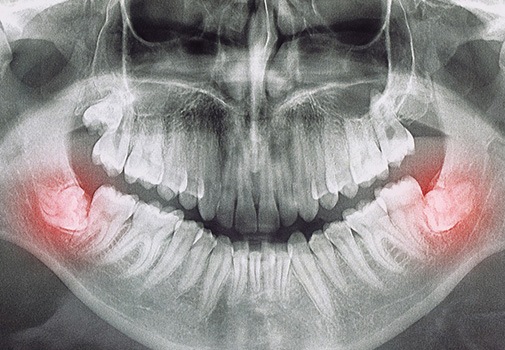

The wisdom teeth are the last set of teeth to come into the mouth, usually appearing between the ages of 16-25. However, most people don’t have enough room for them. So they become trapped within the gum and bone (impacted) or press on the nearby teeth, which can lead to pain, infection, bone loss, and other unpleasant symptoms. As a board-certified oral surgeon in Medford with significant experience removing wisdom teeth, Dr. Keyser is able to prioritize a patient’s comfort before, during, and after the procedure. If you or your teen is experiencing wisdom teeth woes, there’s no need to wait for relief—call today to schedule an appointment.

There are two different approaches Dr. Keyser can take for wisdom tooth extraction based on the situation:

Surgical: If the wisdom teeth are partially stuck in the gum and bone, or impacted, then a minor surgery is necessary. With this, any tissue that blocks access to the tooth is moved, and then the tooth is delicately extracted, often in pieces to prevent excessive force on the jaws and to preserve the surrounding anatomy such as the nerves and sinus cavity. The gums are then replaced into their customary position.

- Impaction: If you have wisdom teeth that are impacted, the procedure is more complex. This can lengthen the treatment time, increasing the cost.